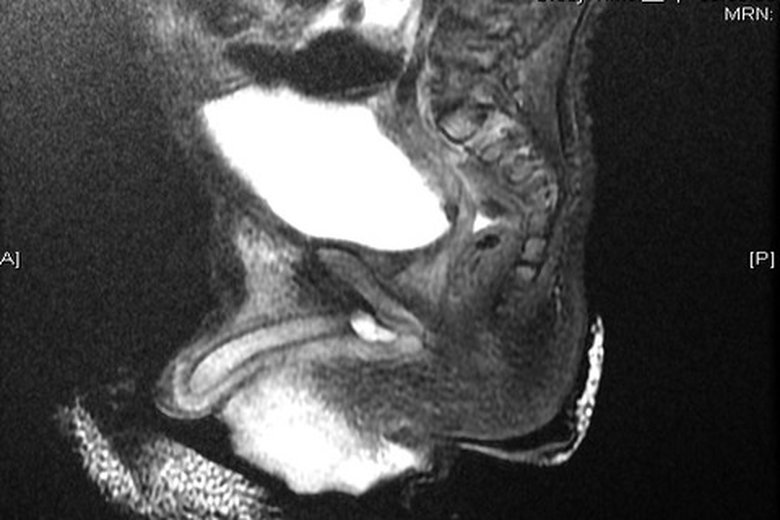

男童罹罕見慕勒氏管囊腫 睪丸單邊萎縮

男童側面腹腔慕勒氏管囊腫斷層照片. (嘉義基督教醫院提供)

【新唐人亞太台 2015 年 10 月 30 日訊】一名五歲男童因先天重度尿道下裂合併睪丸發炎,經3次開刀仍無法解決問題,最近確診罹患罕見的慕勒氏管囊腫,但因發現太晚,以致睪丸已單邊萎縮。

嘉義基督教醫院兒童外科主任賈書悌表示,這名男童長期因疼痛哭鬧,期間曾開刀3次,仍無法解決睪丸發炎問題。到醫院求診時,以腹腔鏡手術切除及重建男童尿道,但因時間拖太久了,睪丸因多次發炎壞死,已造成單邊萎縮,手術後雖然根除病灶,但多少會影響日後的生育能力。

賈書悌指出,慕勒氏管是男女嬰出生時都會有的器官,女嬰會隨著年齡增長發展為子宮,男嬰會退化消失,但這名男童好像多長了個子宮一樣,這種疾病男嬰發生率不會超過5000分之一。

賈書悌建議,家中有男嬰的家長,若出現先天重度尿道下裂,合併睪丸發炎等不適症狀,極有可能為慕勒氏管囊腫造成,需儘速就醫,以免影響日後的生育能力。